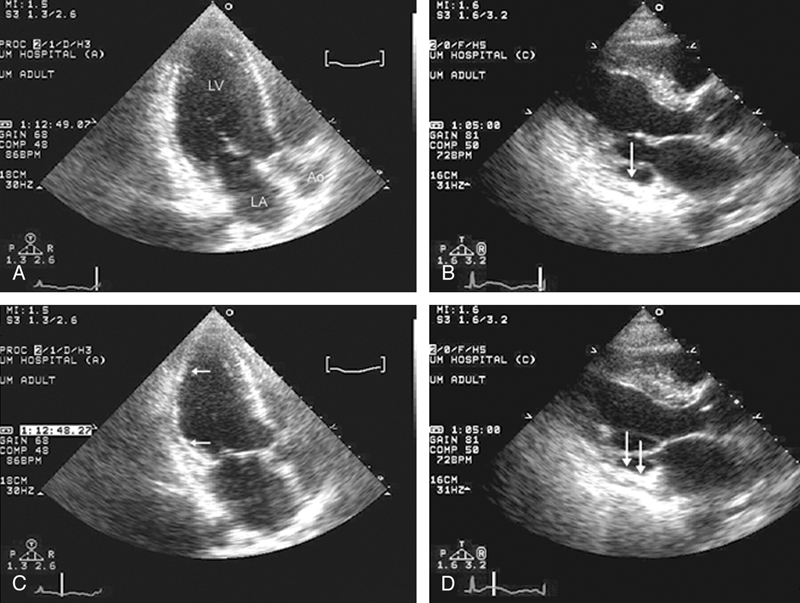

فحوصات تشخيصية لبعض امراض القلب والشرايين التاجية